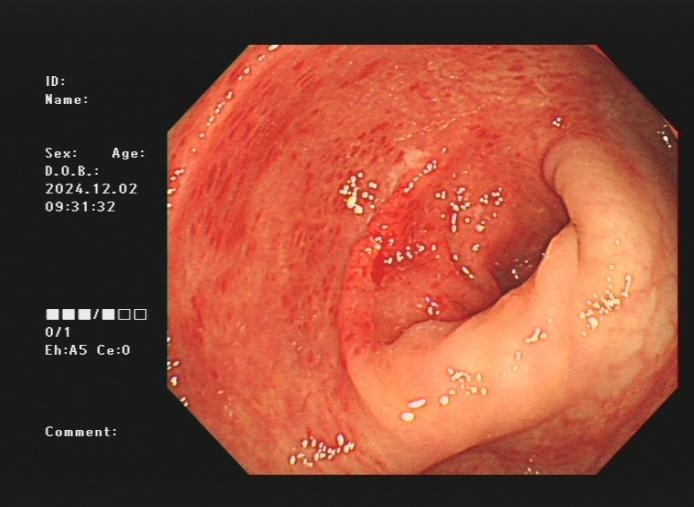

3.下消化道出血常见病因包括痔疮、肛裂、肠息肉、结肠癌、肠道憩室、炎症性病变(溃疡性结肠炎、缺血性肠炎、 感染性肠炎等)。以下是一些常见的下消化道出血内镜图片:

结肠癌、溃疡性结肠炎及缺血性肠病出血